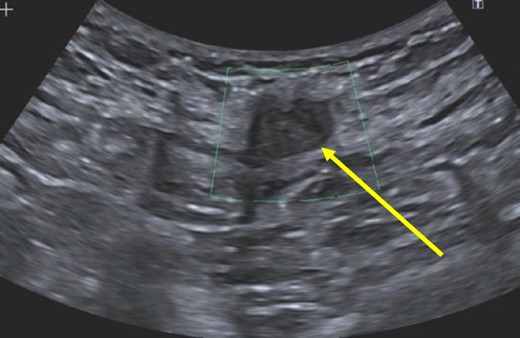

A 38-year-old female with past medical history of hypertension, migraine headaches, and anemia as well as past surgical history of two Cesarean sections presented to our general surgery clinic with a painful abdominal mass at the left lateral aspect of her Pfannenstiel incision. She reported that her most recent Cesarean section was 4 years ago with recurrent pain over the incision for about 2 years. Of note, 2 years prior to presentation at our clinic, she was seen by a general surgeon for similar symptoms and was found to have two subcutaneous nodules at the lateral edge of the Pfannenstiel scar. Ultrasound of the region at that time showed two hypoechoic, nonvascular, and non-fluid-filled subcutaneous nodules suggestive of suture granulomas (Fig. 1). Since then, she had experienced intermittent discomfort. More recently, each month at the time of menstruation, she stated that the mass would enlarge and become more painful. After menstruation, the mass would decrease in size and the pain would recede. On this visit, ultrasound revealed a heterogeneous vascular soft tissue mass measuring 4.1 × 3.3 × 4.4 cm, suspicious for endometrioma in the setting of her clinical history (Fig. 2).

Heterogeneous, vascular nodule (arrow) measuring 4.1 × 3.3 × 4.4 cm, suggestive of endometrioma.